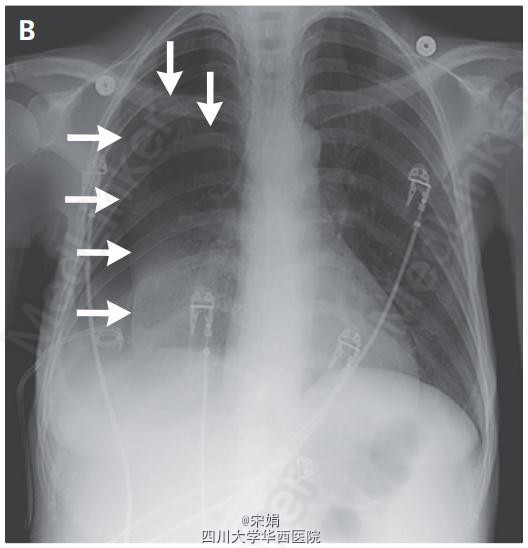

患者为46岁女性,呼吸困难就诊,患者因终末期肝病出现复发性肝性胸水,需要反复胸腔穿刺。胸部检查发现右肺无呼吸音。胸片显示液气胸(图A,箭头显示气胸,星号显示液胸)。遂留置猪尾导管引流胸腔积液,但气胸仍持续存在(图B,箭头)。

胸部CT扫描发现肺萎陷(伴脏层胸膜增厚,且无气管内梗阻表现(图C)。